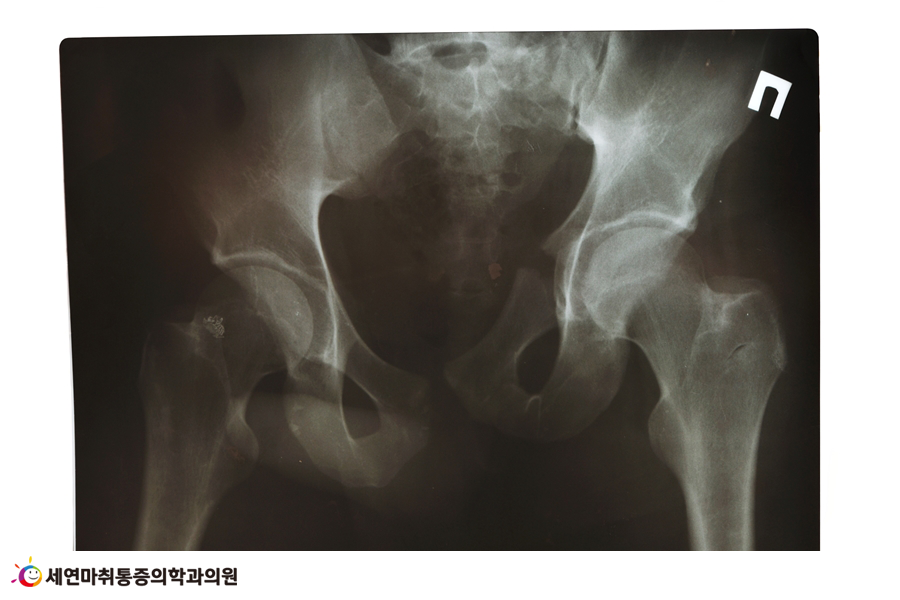

얼마 전 저를 찾아온 한 여성 환자는 출산 이후부터 골반통이 계속되고 골반틀어짐 등 체형 불균형으로 인해 도수치료를 받고 있습니다.

임신과 출산으로 골반 근육이 약해지는 등 골반 건강이 악화된 경우인데, 골반통과 허리 통증이 심하고 경미한 척추측만증 증상을 보였으며, 골반틀어짐으로 인한 하체 비만 및 체형 변화로 인해 우울감을 느끼는 분이었습니다.

다행히 세연통증재활센터에서 산전·산후관리클리닉을 통해 골반틀어짐을 교정하는 도수치료 시행 후, 극심한 통증을 호소했던 골반통과 허리통증이 완화되었습니다.